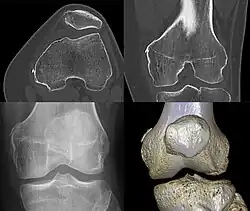

Pellegrini–Stieda syndrome (also called Stieda disease and Köhler–Pellegrini–Stieda disease) is the ossification of the superior part of the medial collateral ligament of the knee. It is a common incidental finding on knee radiographs. It is named for the Italian surgeon A. Pellegrini (b. 1877) and the German surgeon A. Stieda (1869–1945).[1] While the eponym refers to Pellegrini and Stieda, the condition was first discovered by Köhler in 1903, before any namesakes. Pellegrini-Stieda combines the aforementioned radiographic findings and concomitant medial knee joint pain or restricted range of motion.[2]

Diagnosis is typically made on radiographs demonstrating the Pellegrini-Stieda syndrome sign accompanied by pain or restriction of range-of-motion of the knee joint.[2] Pellegrini-Stieda syndrome sign is typically described by a longitudinally linear opacity, which is a process that is describes characteristic of calcification in the soft tissue located medial to the medial femoral condyle.[2] This calcification seen on imaging represents the ossification of the medial collateral ligament, which typically does not develop until approximately three weeks after the initial injury.[2]It is important to note to distinguish this radiographic finding from that of a medial femoral condyle avulsion fracture, which is an injury in which a pulling force of a tendon or ligament fractures away a piece of the bone from its attachment site.[2]

Alternative classification syndrome for Pellegrini-Stieda lesions of Type 1 through Type 4 based on their location:[2]

- Type 1- is referred to as a beak-like appearance and describes the ossification arising from the femur and extending inferiorly in the medial collateral ligament.

- Type 2-is defines a tear-drop pattern, localized within the medial collateral ligament without any attachment to the femur.

- Type 3-presents as an elongated ossification superior to the femur lying in the distal adductor magnus tendon.

- Type 4-is also characterized as a beak-like appearance arising from the femur. However, there are some cases where this ossification extends into both the medial collateral ligament and adductor magnus tendon. In then, the original attribution of the syndrome to the medial collateral ligament may now be outdated as many publications have suggested concomitant and even sometimes preferential involvement of the adductor magnus tendon, medial head of the gastrocnemius, or medial patellofemoral ligament.[2]